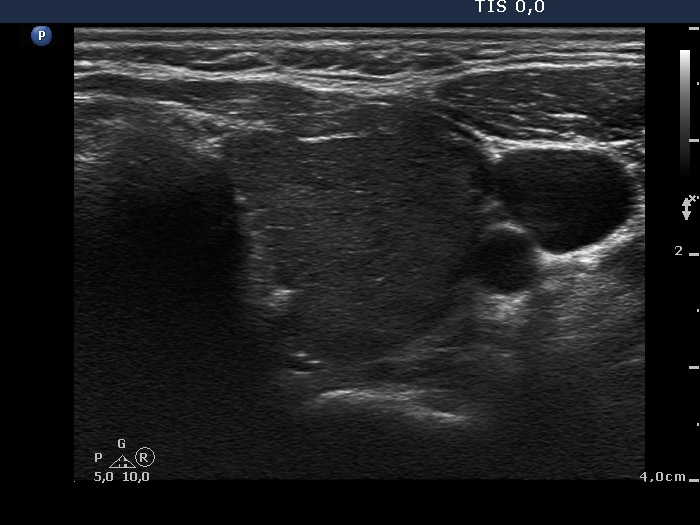

Consecutively operated patients with autoimmune thyroid disease - case 12 (1427) (ultrasonographic picture 5)

Left lobe, transverse view. The pattern is similar to that of the right lobe.